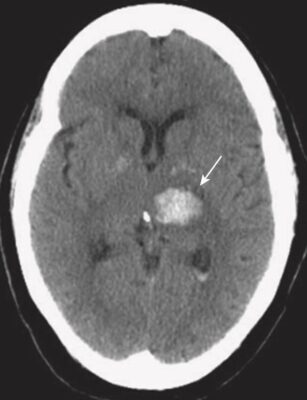

- Trong phần lớn các trường hợp, có tăng huyết áp kèm theo. Khoảng 60% trường hợp xuất huyết do tăng huyết áp xảy ra ở hạch nền. Các vùng khác thường liên quan là đồi thị, cầu não và tiểu não (Hình 18).

- Máu tươi mới thoát mạch hematocrit bình thường có thể nhìn thấy như là tăng tín hiệu trên phim chụp CT não không cản quang ngay sau biến cố (xem Hình 18). Điều này được cho là do protein trong máu (chủ yếu là hemoglobin).